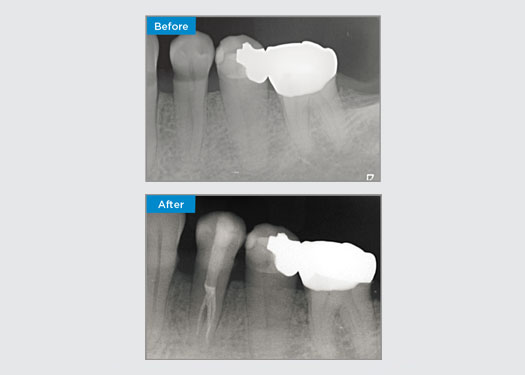

Der Patient stellte sich mit einer irreversiblen Pulpitis an Zahn 46 vor. Auf dem präoperativen Röntgenbild zeigt sich Zahn 46 mit einer zusätzlichen distalen Wurzel (Radix Entromolaris-Zahnmorphologie). Ein DVT-Scan hat das Vorhandensein einer DL-Wurzel mit starker Wurzelkrümmung bestätigt. Für diese kritische DB-Wurzel ist eine sorgfältige Feilenauswahl entscheidend.

Dr. Jack Lin, Endodontist, Sydney, NSW Australien

In dieser Situation ist die Erhaltung der Zahn-/Wurzelstruktur von entscheidender Bedeutung, um das Risiko von Vorsprüngen, Verschiebungen, Abrissen, Perforationen und Wurzelfrakturen zu verringern. Fallauswahl, Diagnose und Behandlungsplanung sind wichtig. Die Auswahl von endodontischen Feilen, die flexibel und effizient sind und die natürliche Wurzelanatomie respektieren, ist entscheidend.